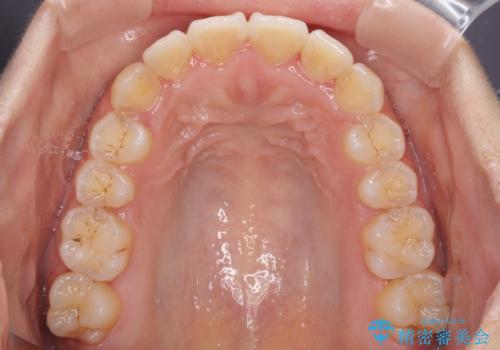

前歯のデコボコをインビザラインでスッキリと

- 上下前歯のデコボコを気にして来院された患者様です。

デコボコを解消する過程で、歯列の拡大により口元が突出する可能性があったため、4本の親知らずを抜歯しておき、歯列全体が後方に移動するように設計し、インビザラインにて矯正治療を行うこととしました。

日々の装着時間をしっかりと守って治療の臨んでくださったため、治療前のシミュレーションに近い形で矯正治療を進めて行くことができました。